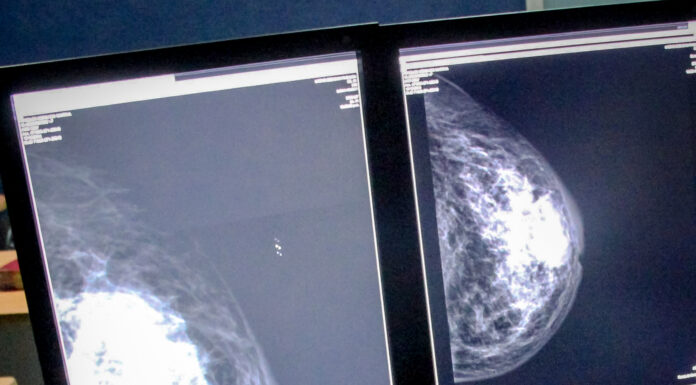

Yuri Nayelli Becerra Grande, Coordinadora Estatal del Cáncer en la Mujer de la Secretaría de Salud en Hidalgo (SSH), informó que, para la semana epidemiológica número 13, se han diagnosticado 42 nuevos casos de cáncer de mama en nuestro...